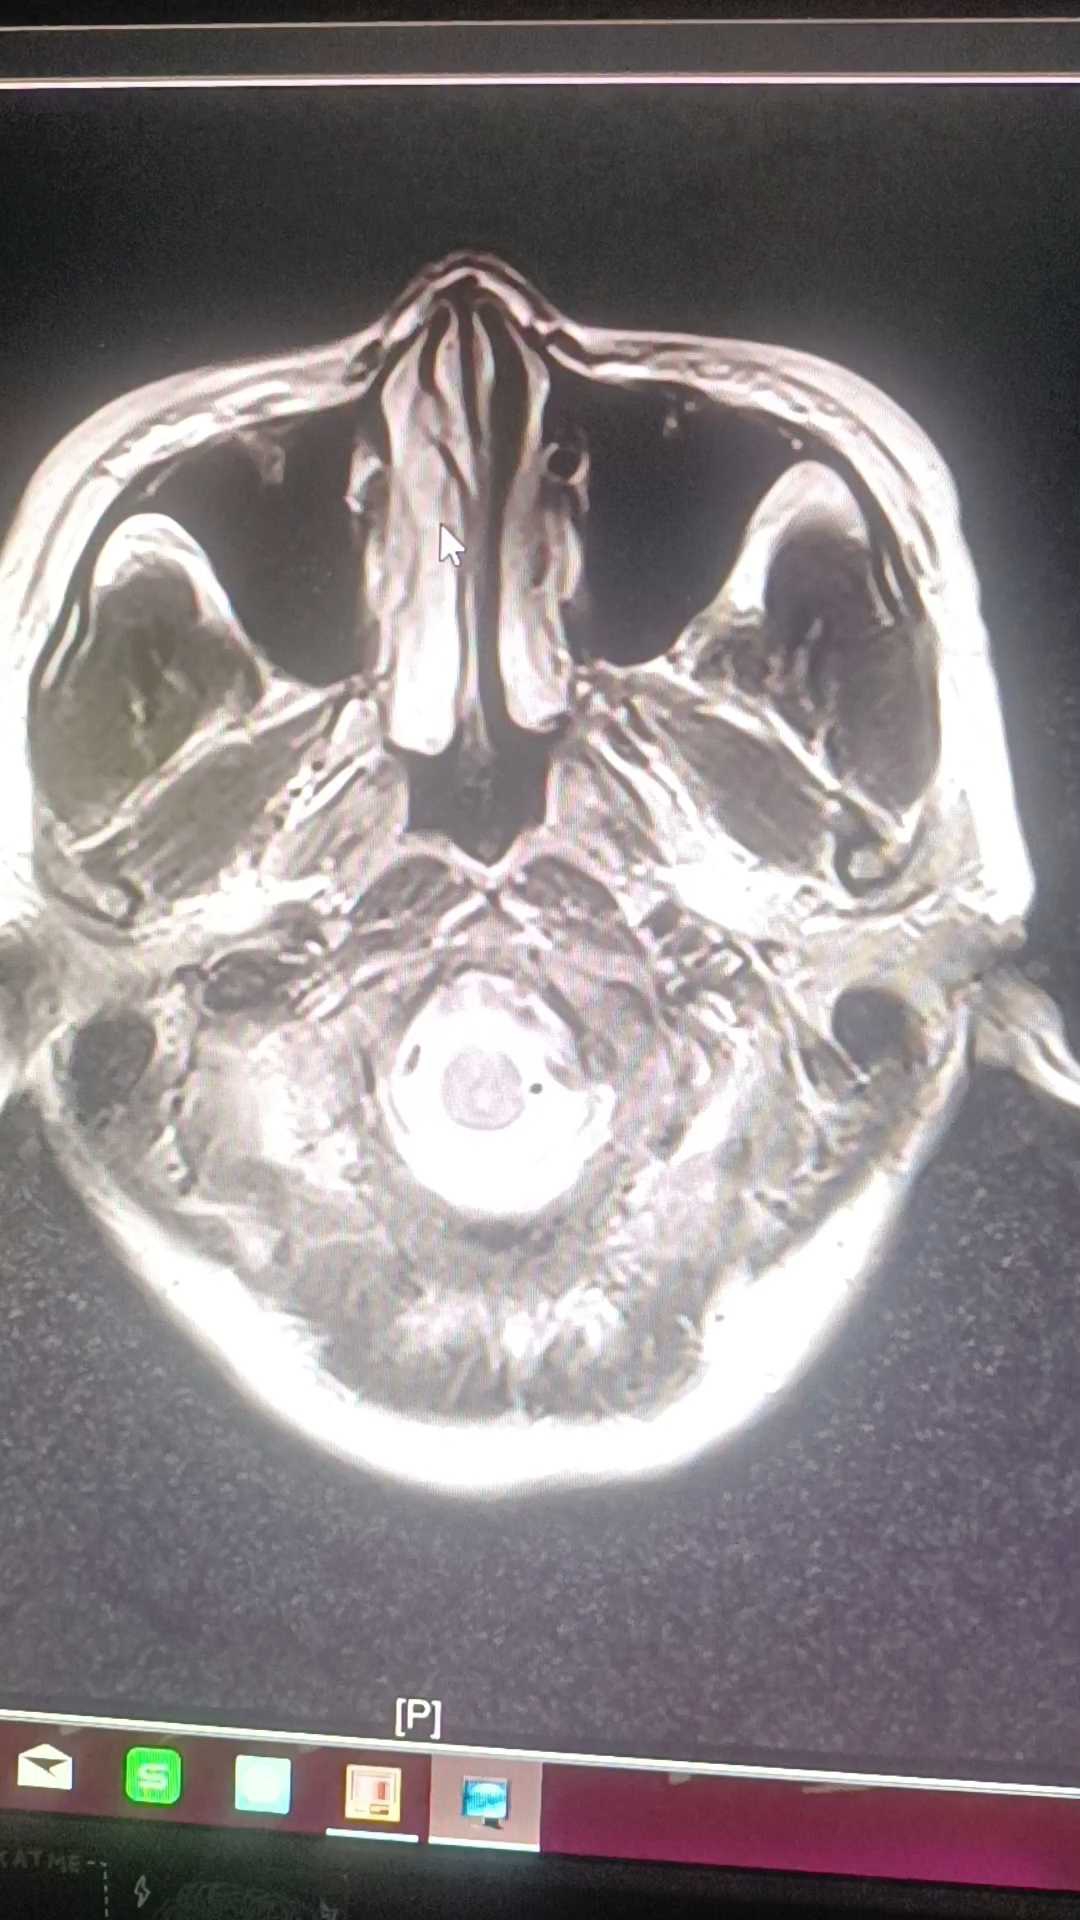

患者,37岁,女性,头部外伤后头痛,头晕,恶心2天入院。自诉右耳听力下降,伴耳鸣,行相关检查如下